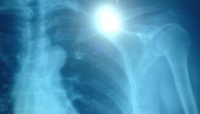

因外伤引起者为外伤性脱位;因关节病变引起者为病理性脱位;脱位后,关节面完全丧失对合关系者为完全脱位;部分丧失者为半脱位。外伤性脱位较多见,且多发生在青壮年。最易发生脱位的关节是肘关节,其次是肩及髋关节。伤后关节局部疼痛、肿胀、活动障碍及出现畸形,多可据此作出诊断。为了确定脱位的方向、程度及是否合并骨折,X线检查是必要的。对脱臼者应及时进行手法复位,越早越好。复位后应使关节固定于稳定位置2~4周;解除固定后还应进行主动的功能锻炼,以利恢复关节功能。如果手法复位失败,应行手术切开复位。

肩部关节就如同一个球在手套中的感觉一样,比较不稳固。若受到打击,跌跤,抽筋,用力丢球等,都极有可能会造成肩部脱臼。百分的病患,其肱骨头会被迫向前,肩关节脱臼还会合并上肢骨折,兼韧带裂伤或血管及神经受伤。病患除无法动弹外,有时会因剧烈疼痛而昏倒,若仅有肩部痛而没有任何外伤的情况下,就必须先将病患发生的原因来评估,如疼痛的位置,感觉,伤侧与健侧运动功能之比较,衰弱的情形与无力感等。